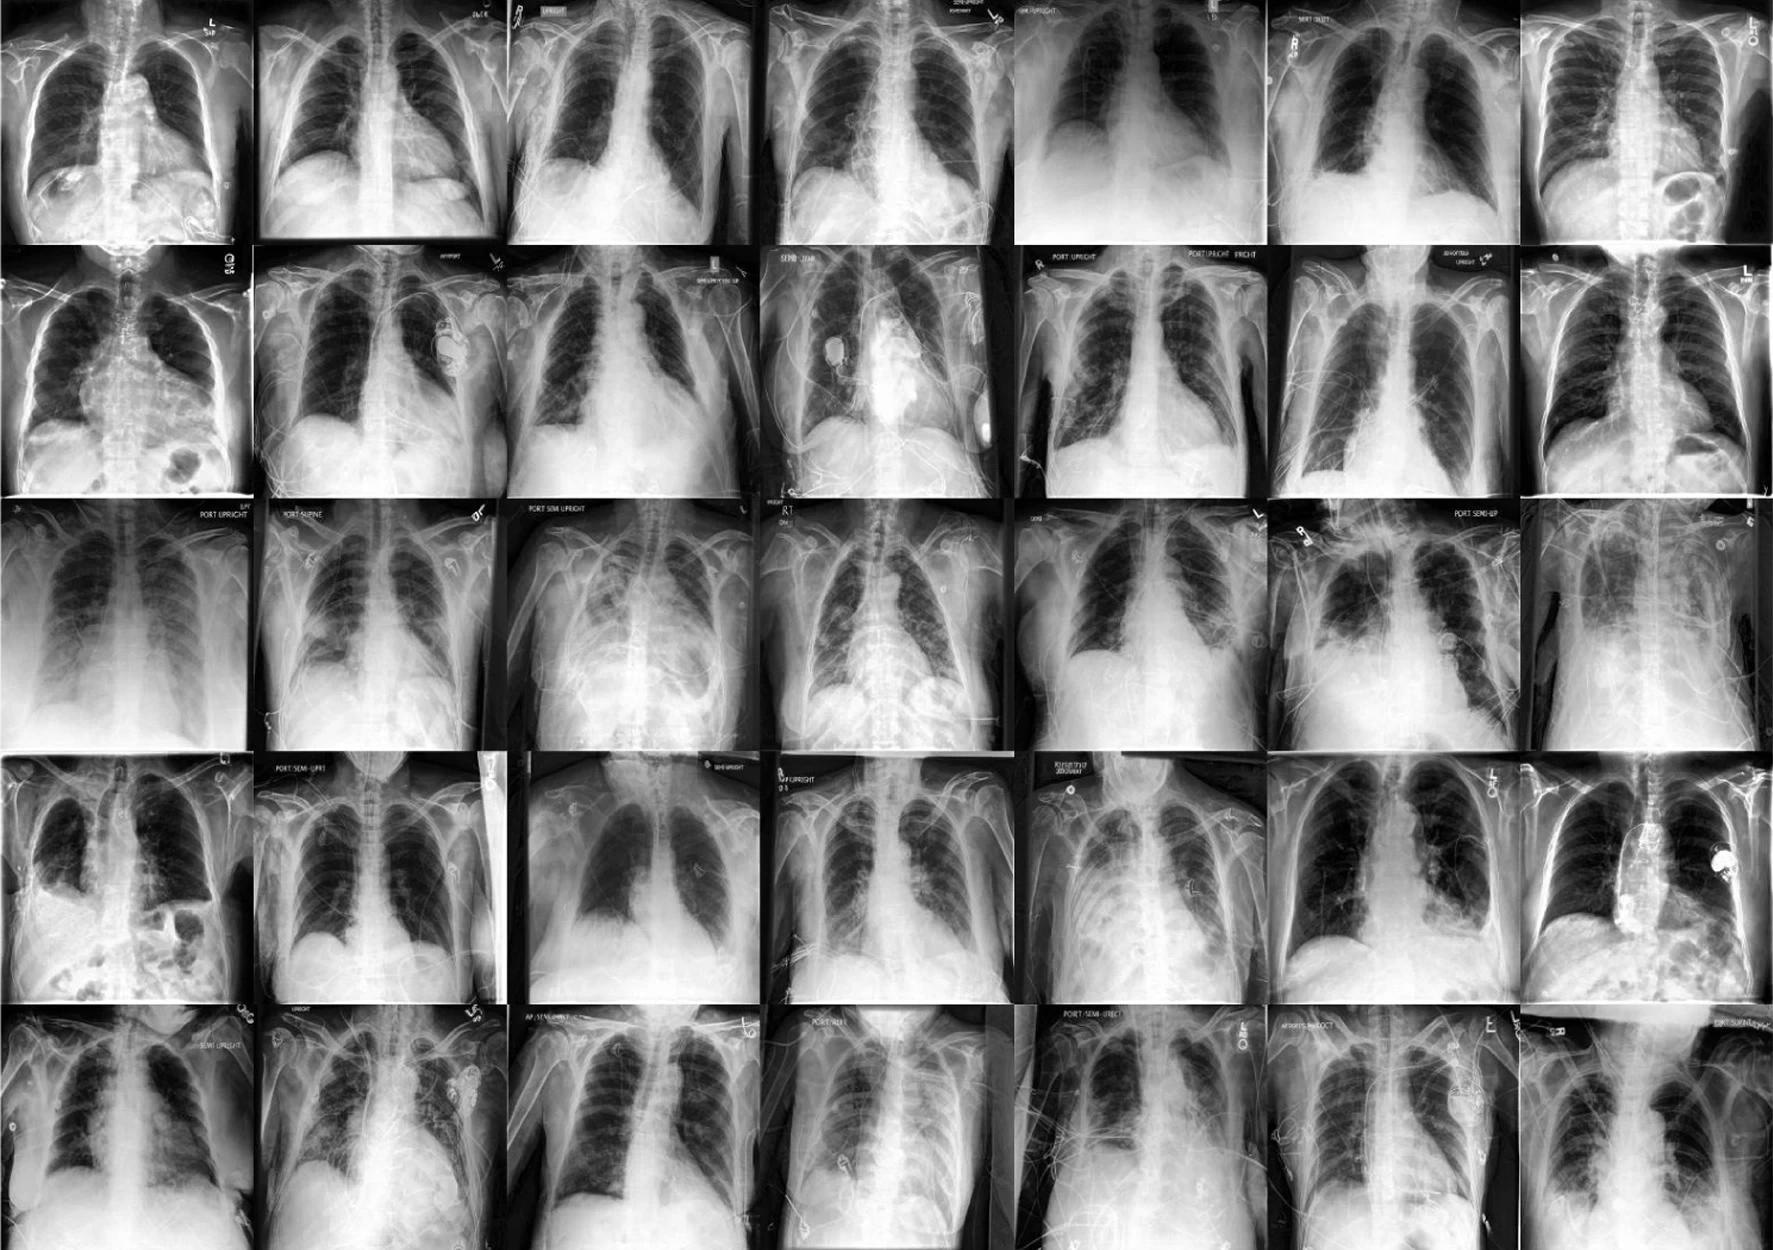

In a recent study published in the journal Nature Medicine, researchers used diffusion models for data augmentation to increase the robustness and fairness of medical machine learning (ML) models in three medical imaging contexts: histopathology, chest X-rays, and dermatological images.

In the present study, researchers employed diffusion models to examine medical imaging situations such as histology, chest X-rays, and dermatological pictures. They used these photos to enhance the reliability and fairness of medical machine-learning models. They also utilized unlabeled data to track data dispersion and supplement actual samples. The project sought to expand the training dataset in a steerable and programmable manner.

Researchers used two big public radiology datasets, CheXpert and ChestX-ray, to create generative and diagnostic models for chest X-rays. After training on 201,055 chest X-ray instances, dermatologists evaluated the model's ability to capture primary characteristics on 488 synthetic pictures from regular and high-risk classes. They assessed the picture quality to offer a diagnosis for up to three of the approximately 20,000 common illnesses.